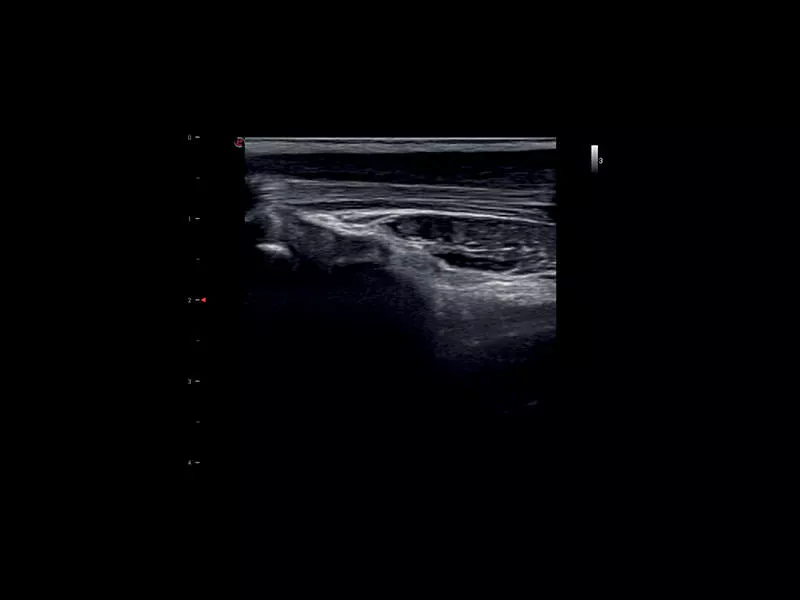

MyLab™9 Platform - High Frequency MSK Imaging with HD Zoom

MyLab™9 Platform - High Frequency MSK Imaging with HD Zoom